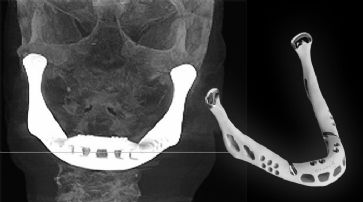

Erstes Kiefertransplantat mit 3D-Drucker hergestellt

3D-Drucker stellt Nervenbahnen aus Silikon her

Forscher der University of Minnesota haben mittels 3D-Druck Nerven rekonstruiert. Das Verfahren könnte jährlich über 200'000 Menschen mit Verletzungen oder Erkrankungen helfen.